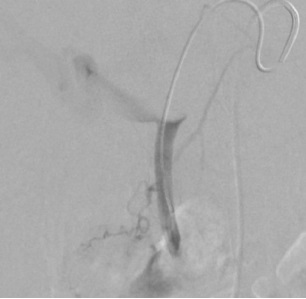

| 锚定技术 anchor scaffolding technique,通常和脚手架技术(scaffolding technique)联合应用,在临床上主要用于大血管或/和高血流血管的阻塞。其定义如下

1. 大动脉阻塞 large artery occlusion

2. 锚定弹簧栓子在一侧分支anchor coil in side-branche

3. 弹簧栓子直径>血管直径 coil diameter > vessel diameter

4. 前进到前端然后释放 go to and fro and push

如果第一个推式弹簧栓子可能应用锚定技术就不要担心其稳定性